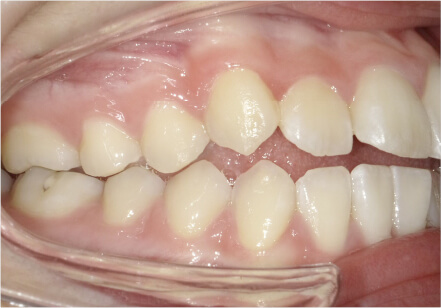

叢生の症例

41歳

女性

横から見た時のガタガタが気になる

カウンセリング・診断結果

インビザライン、正中は上11に合わせていく、抜歯・拡大装置・IPR・アタッチメントOK

治療内容・方法

アライナー矯正

術後の経過・現在の様子

クリアライナー使用

痛み・歯根吸収・歯肉退縮・虫歯・後戻り

費用・治療期間

880,000円、7ヶ月